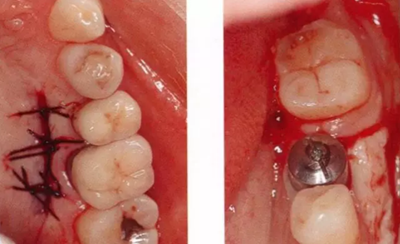

▲圖6-4,5

圖6-4 第二次手術前的(牙合)面照。牙槽嵴頂?shù)缴鄠戎g有一定程度的角化齦,但是頰側有凹陷,在這種狀態(tài)下進行治療,會遺留牙槽嵴形態(tài)異常的問題。

圖6-5 一定程度上保留了舌側的角化齦,頰側使用內斜(從舌側向頰側)切開的方式,從舌側切開牙槽嵴的角化齦,形成半厚瓣。

▲圖6-6,7

圖6-6 從上頜腭側采集移植片。

圖6-7 為增大牙槽嵴、獲得角化齦,在頰側使用吸收性縫合線對移植片進行骨膜縫合,之后在移植片上蓋上齦瓣,縫合并固定在根尖側。

▲圖6-8,9

圖6-8 第二次手術完成后的(牙合)面照。

圖6-9 第二次手術后2個月,頰舌側都獲得了充足的角化齦,頰側牙齦的形態(tài)呈現(xiàn)凸面狀。